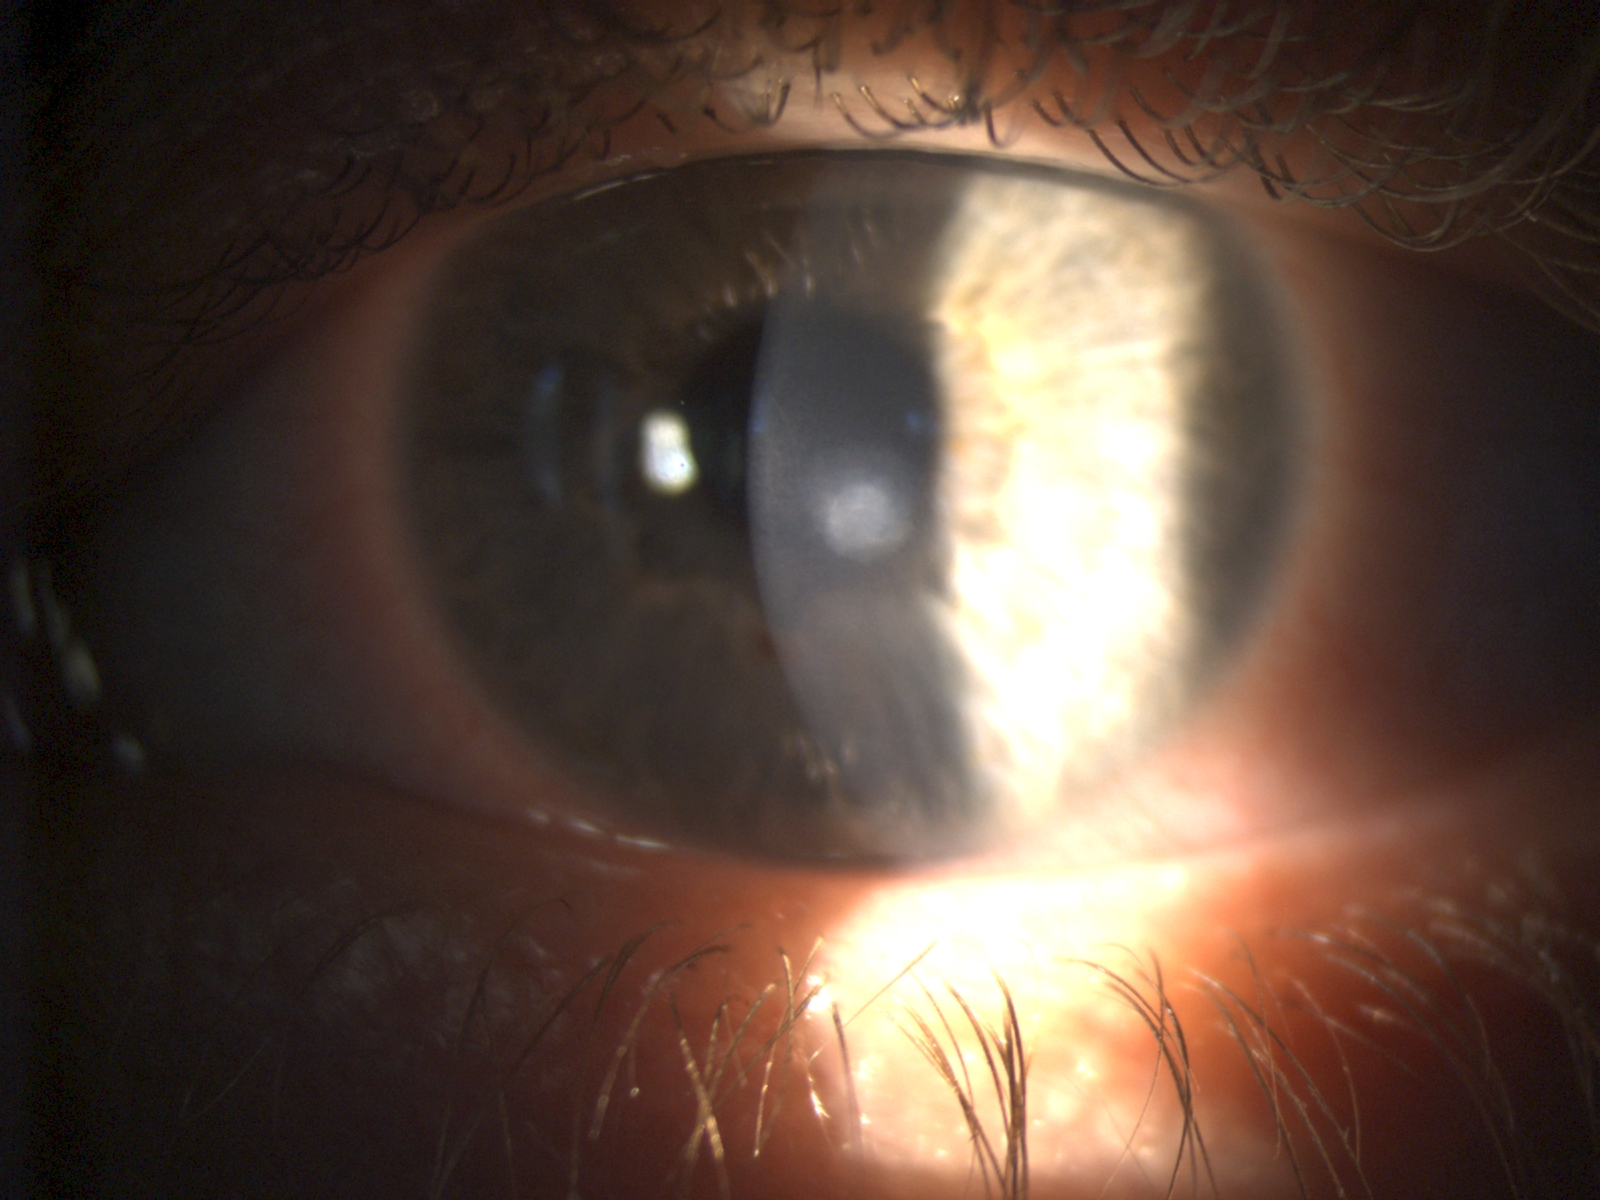

Bijvoorbeeld: wanneer oogdrukken wat aan de hoge kant zijn, of wanneer er een familiair verband is met glaucoom, kan een uitbreiding op de glaucoomscreening nodig zijn. Dan worden extra onderzoeken, specifiek op deze vermoedens, uitgevoerd.

- Verhoogde oogdruk of familiaire belasting met glaucoom

Afhankelijk van de indicatie kunnen aanvullende onderzoeken worden uitgevoerd, zoals een gezichtsveldmeting, OCT-scan van de oogzenuw, of uitgebreide beoordeling van het netvlies met pupilverwijdende druppels.